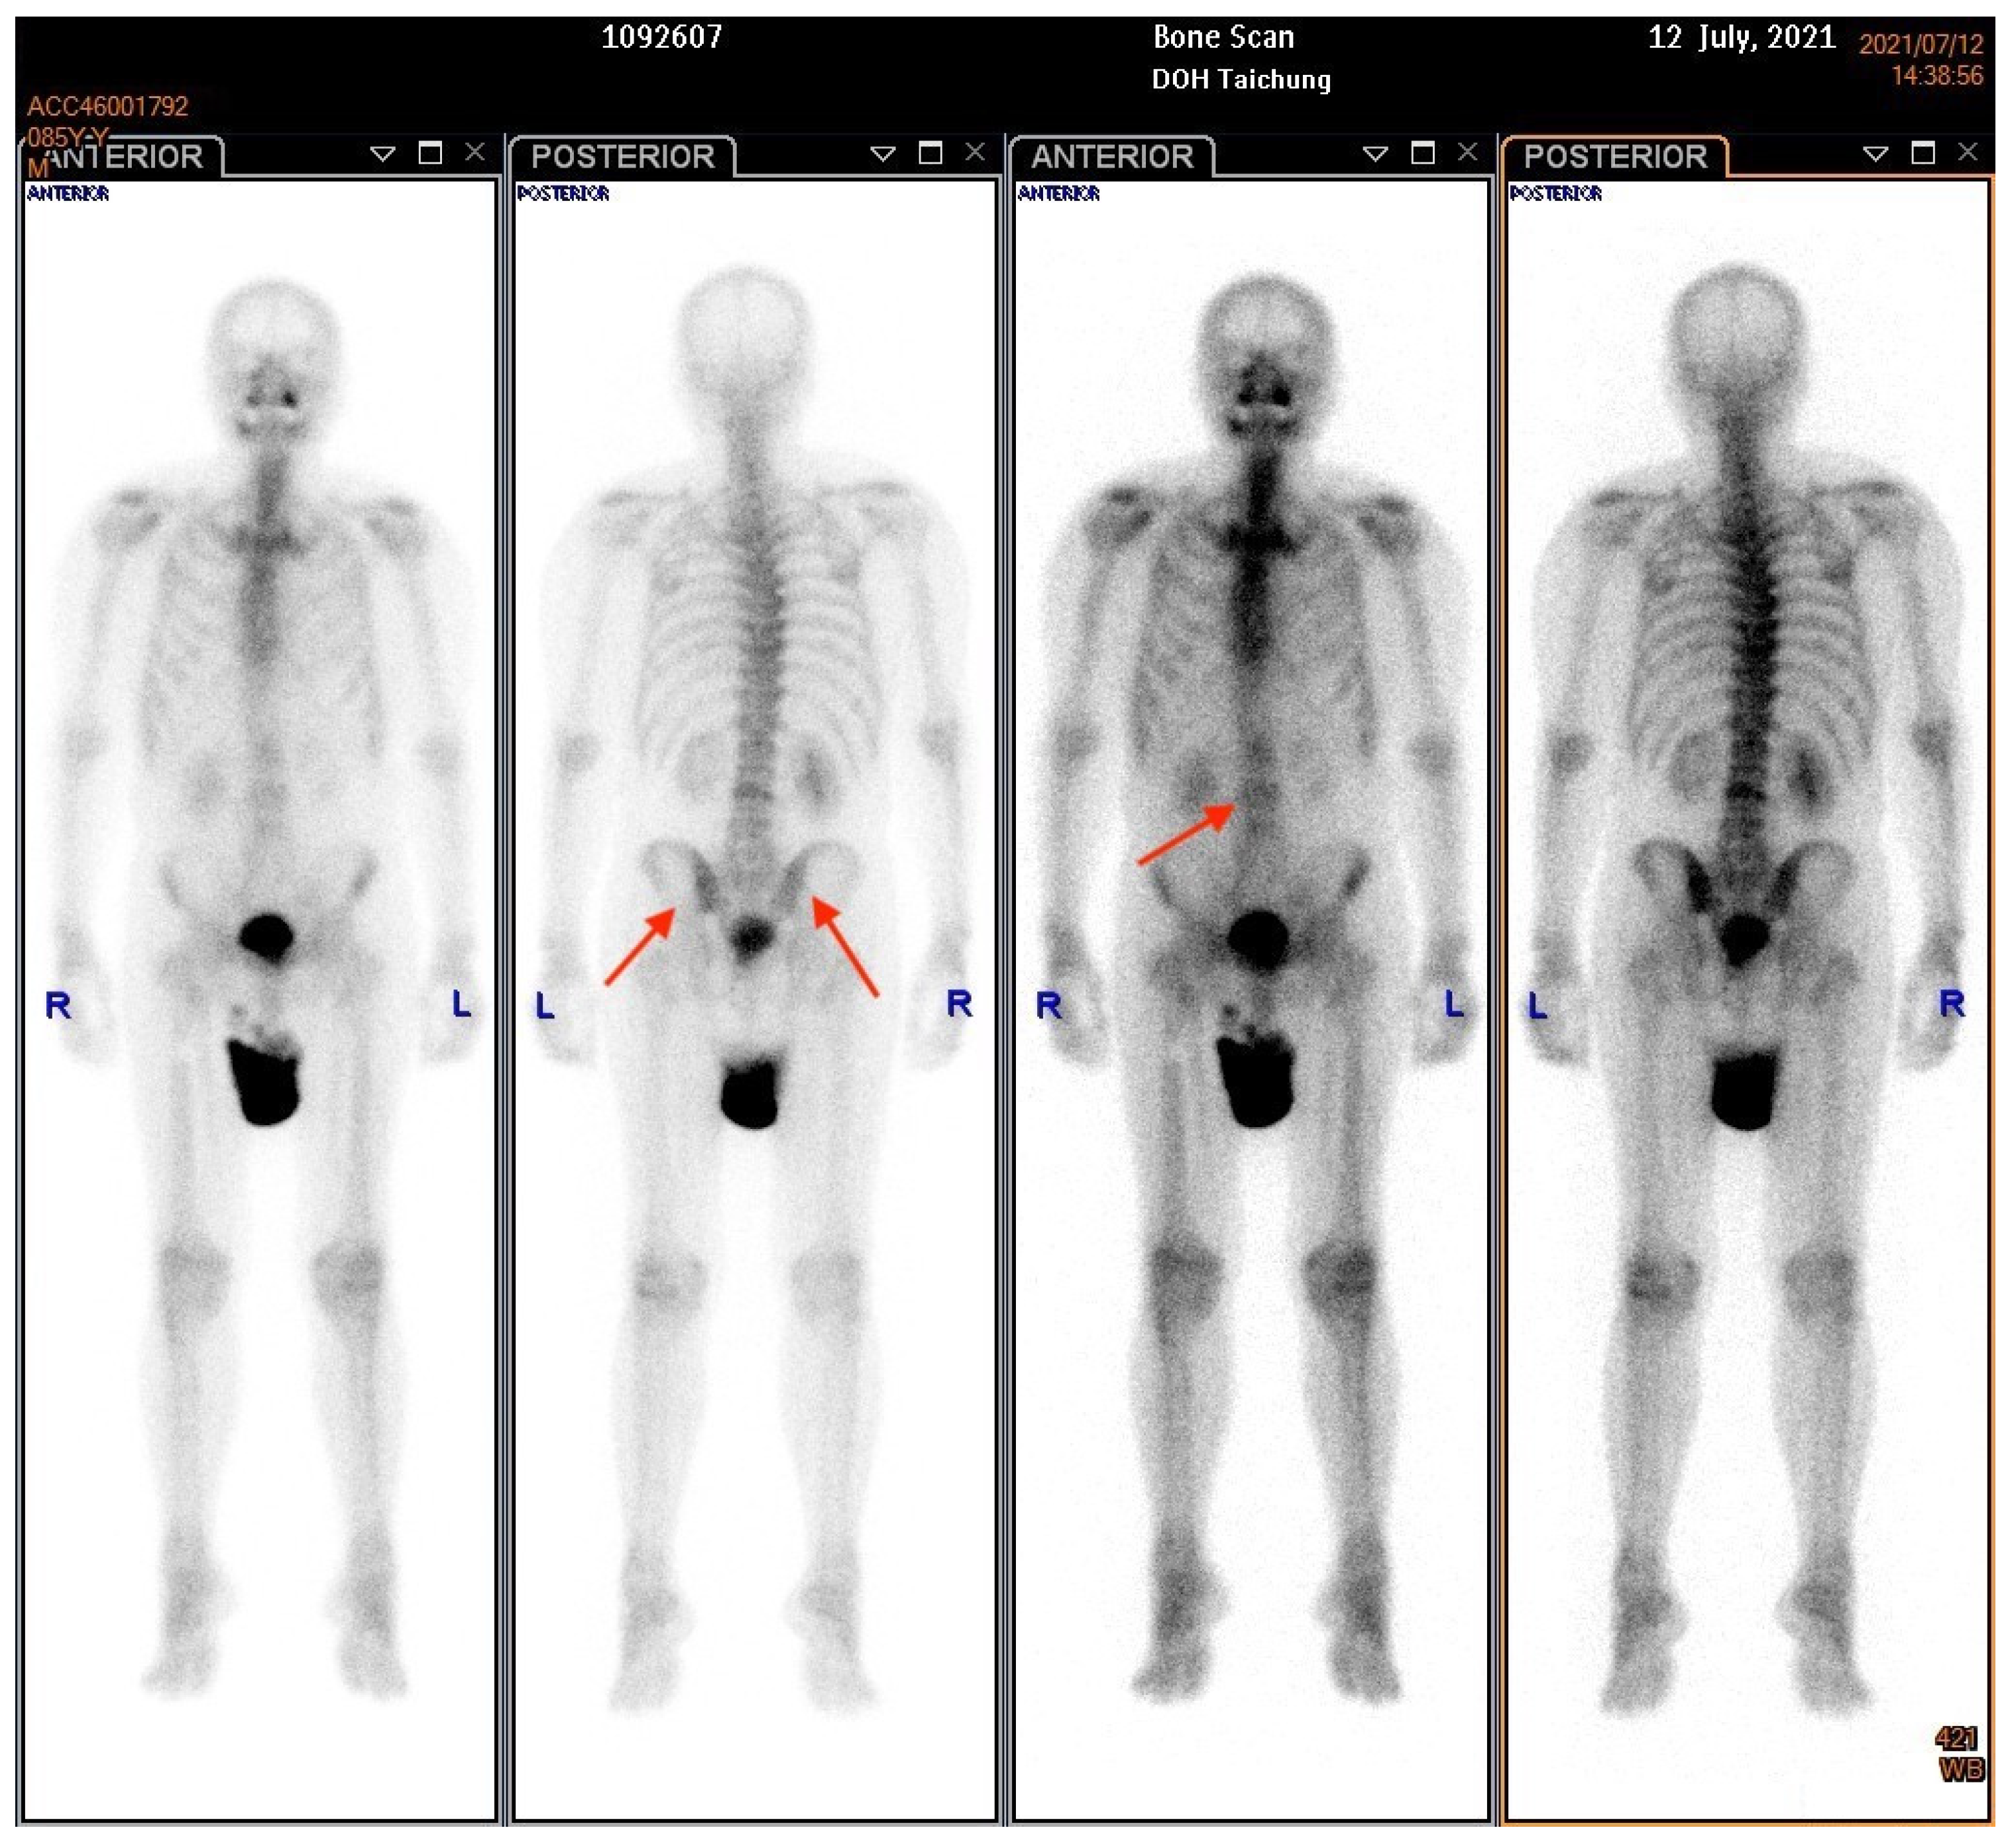

An 85-year-old male patient presented with a history of diabetic nephropathy and benign prostate hyperplasia (BPH) with lower urinary tract symptoms (LUTS) under oral alfa-blocker treatment. He was a non-smoker and had no family history of prostate cancer. His initial PSA level was 4.2 ng/dL, and transrectal ultrasonography showed that his prostate was 60 g in weight on 3 April 2019. He underwent PAE by a cardiologist on 18 April 2019, after an outpatient visit for hypertension. His PSA level decreased to 1.6 ng/dL one month later, but then gradually increased to 2.83 ng/dL three months later and 2.91 ng/dL five months later (29 October 2019). He underwent transrectal ultrasonography again six months postoperatively, which showed that his prostate weighed 23 g. He was then lost to follow-up until 2021. He returned to our outpatient clinic on account of dysuria, urge incontinence and perineal discomfort in March 2021. As pyuria was found in a urine routine test, he was treated with antibiotics initially. His PSA level was 15.41 in March 2021. He did not respond well to oral medications for LUTS, and he was then referred to urologic outpatient services due to acute urinary retention on May 18th. His serum PSA level was 12.58 ng/dL, and an echogram showed a prostate weight of 97 g. A digital rectal examination (DRE) revealed a firm prostate with an irregular surface, and malignancy of the prostate was highly suspected. We then performed a transrectal prostate biopsy and TURP on 29 June 2021. The intraoperative findings were a papillary lesion at the surface of necrotic tissue at the transition zone, and the total resected chips weighed 61 g. The pathology report eventually showed adenocarcinoma, Gleason score 5 + 5 = 10 (>5%). An abdominal computed tomography revealed multiple lymph node metastases at the paraaortic area (Figure 1), and a bone scan revealed boney metastasis at the L-spine (Figure 2). The clinical stage was cT2cN1M1b. He was then treated with regular hormone therapy. The last checked PSA value was 1.5 ng/dL on 15 June 2022. Written informed consent was obtained from the patient for the publication of this case report.

Figure 2.

A bone scan demonstrated multiple boney metastases over the l-spine and pelvic wing. The arrows indicate the boney metastasis sites.